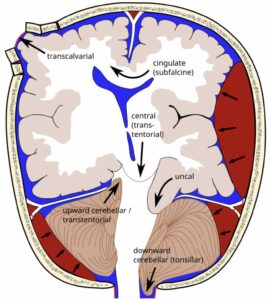

Hvorfor er forhøjet intrakranielt tryk et problem? Det er det selvfølgelig fordi det er en almindelig årsag til død ved meningitis, og det er det også, fordi det er forbundet med risiko for herniering. Her er en illustration fra wikipedia af de forskellige måder hjernen kan herniere på, hvis man har brug for at blive mindet om det

RupertMillard, CC BY-SA 3.0, via Wikimedia Commons

I Durand et al. (1994) var der 40 patienter, der døde af meningitis indenfor 7 dage af diagnosen, og 27 af disse havde obduktionsrapporter, og 8 af disse havde tegn til herniering, alle med temporallapsherniering og cerebralt ødem, fire med cerebellar herniering.